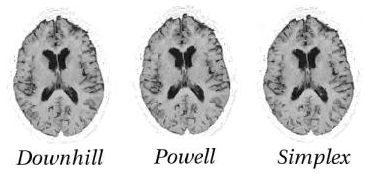

As part of the experiments which investigate optimisation through minimisation of the objective function, I conducted a small survey to compare 3 methods. Figure [*] visually (as opposed to quantitatively) compares the level of refinement reached using the different optimisation methods that I studied. While the imaged brains may show similar results, the time taken to arrive at these results varied significantly. Powell was particularly slow compared to a simple downhill optimisation, which was used in the majority of cases and applied at different scales5.8. In the experiments which this section will show from now on, the only optimiser used was therefore downhill.

Figure: Deciding on an optimiser. A small comparison of different registration optimisation methods. This figure shows the results in the form of chequerboard images or pairs, each corresponding to results of a different optimisation method. The differences are minimal, but the time required to reach these solutions varies significantly depending on the optimisation.